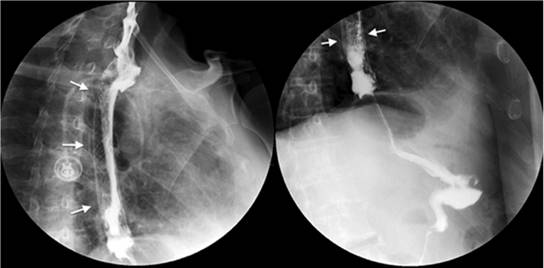

Divertículos esofágicos

Los divertículos son una alteración infrecuente de la integridad de la pared esofágica que se presentan clínicamente con disfagia y regurgitación. Se clasifican según su localización anatómica (esófago superior, medio e inferior). El método de evaluación más eficaz de esta enfermedad son los estudios baritados, ya que proporcionan el diagnóstico definitivo en más del 95% de los casos 18,19,20. El divertículo de Zenker es el divertículo más frecuente del esófago superior y, aunque no hay consenso sobre su exacto mecanismo de formación, se asocia con trastornos de la motilidad y la deglución 18,19 (Figura 7).

Los divertículos del esófago medio se clasifican según su etiología; los divertículos por tracción se asocian con procesos inflamatorios o cicatrices (tuberculosis), mientras que los divertículos por pulsión se asocian con trastornos motores. En el caso de los divertículos epifrénicos, adquieren su nombre por su proximidad al diafragma, se asocian con trastornos de la motilidad esofágica y, algunos de ellos, requieren resección 19,20 (Figura 7).